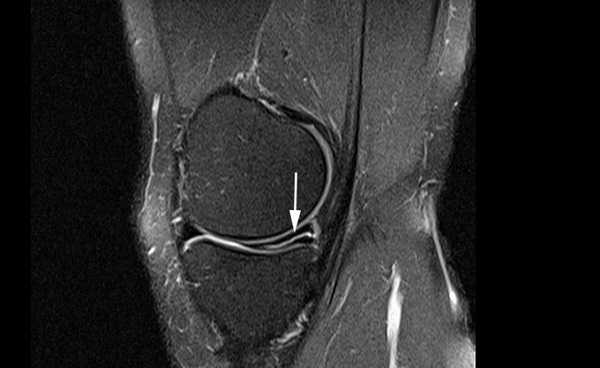

Разрыв заднего рога медиального мениска на снимке МРТ

Признаком повреждения мениска служит наличие линейного гиперинтенсивного очага на Т2-взвешенных изображениях. Участок сообщается с суставной поверхностью хряща, линию разрыва прослеживают на двух и более сканируемых срезах. При этом наблюдают деформацию и фрагментацию пластины.

Томограмма коленного сустава при радиальном разрыве мениска (указан стрелкой)

В зависимости от степени повреждения на снимках МРТ в режиме Т2 видны:

- очаг повышения интенсивности сигнала шаровидной формы, не связанный с поверхностью мениска (I стадия);

- светлый участок линейной формы, не затрагивающий хрящевой край (II стадия);

- повышение интенсивности сигнала распространяется на одну (III a) или обе (III b стадия) суставные поверхности пластины.

Разрыв заднего рога медиального хряща на снимках, выполненных в разных режимах, стрелка указывает на нарушение целостности пластины